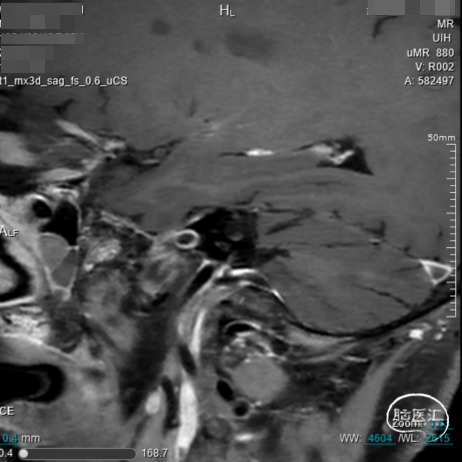

➢术前HMRI

4.CTA、MRI、DSA证实右侧大脑中M1闭塞,闭塞长度<1cm。

通过临床症状、CTP、HMRI确定责任血管,评估存在明显低灌注、闭塞长度、闭塞性质等,我科一般在急性发病后2周至2个月内选择开通,过早可能增加出血风险,过晚可能开通失败等。